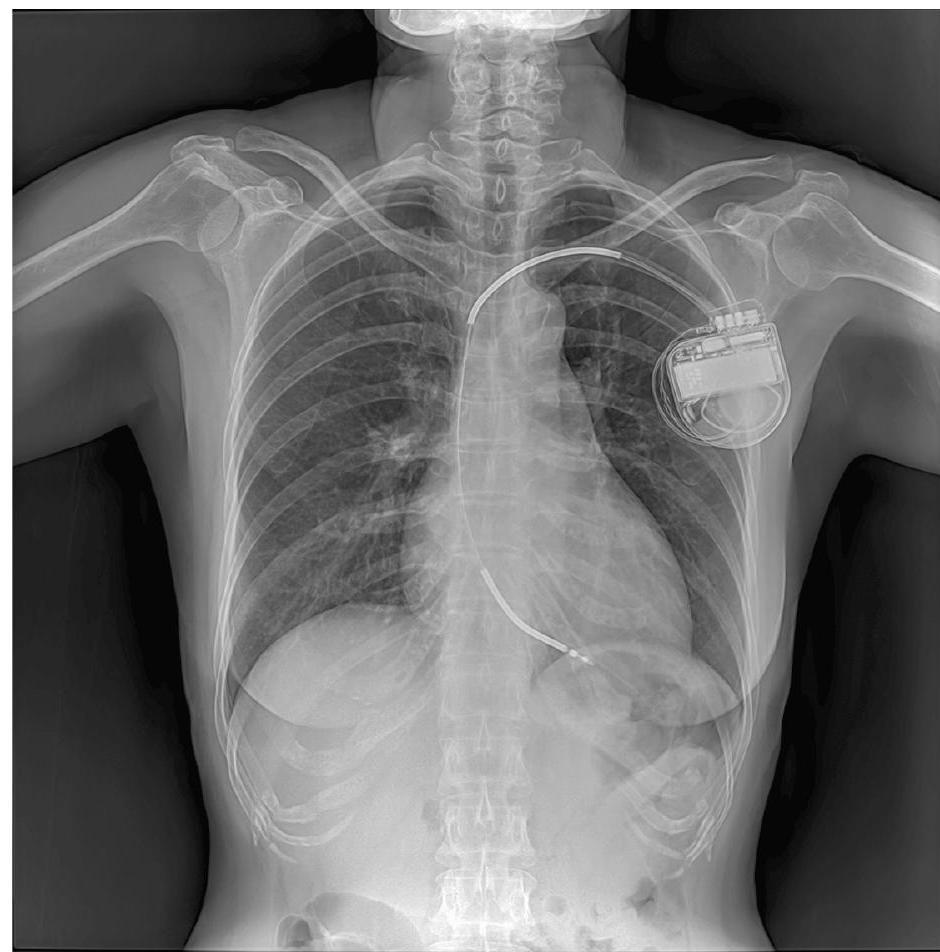

Bij mensen met het lange-QT-syndroom (LQTS) is de impulsgeleiding van het hart verstoord. Dat is zichtbaar op een ecg (elektrocardiogram, afbeelding 1). Het QT-interval is bij hen langer dan normaal. Het hartritme kan daardoor bij inspanning ontregeld raken. De hartkamers kunnen dan abnormaal gaan samentrekken, wat kan leiden tot duizeligheid, bewusteloosheid of zelfs een acute hartstilstand.